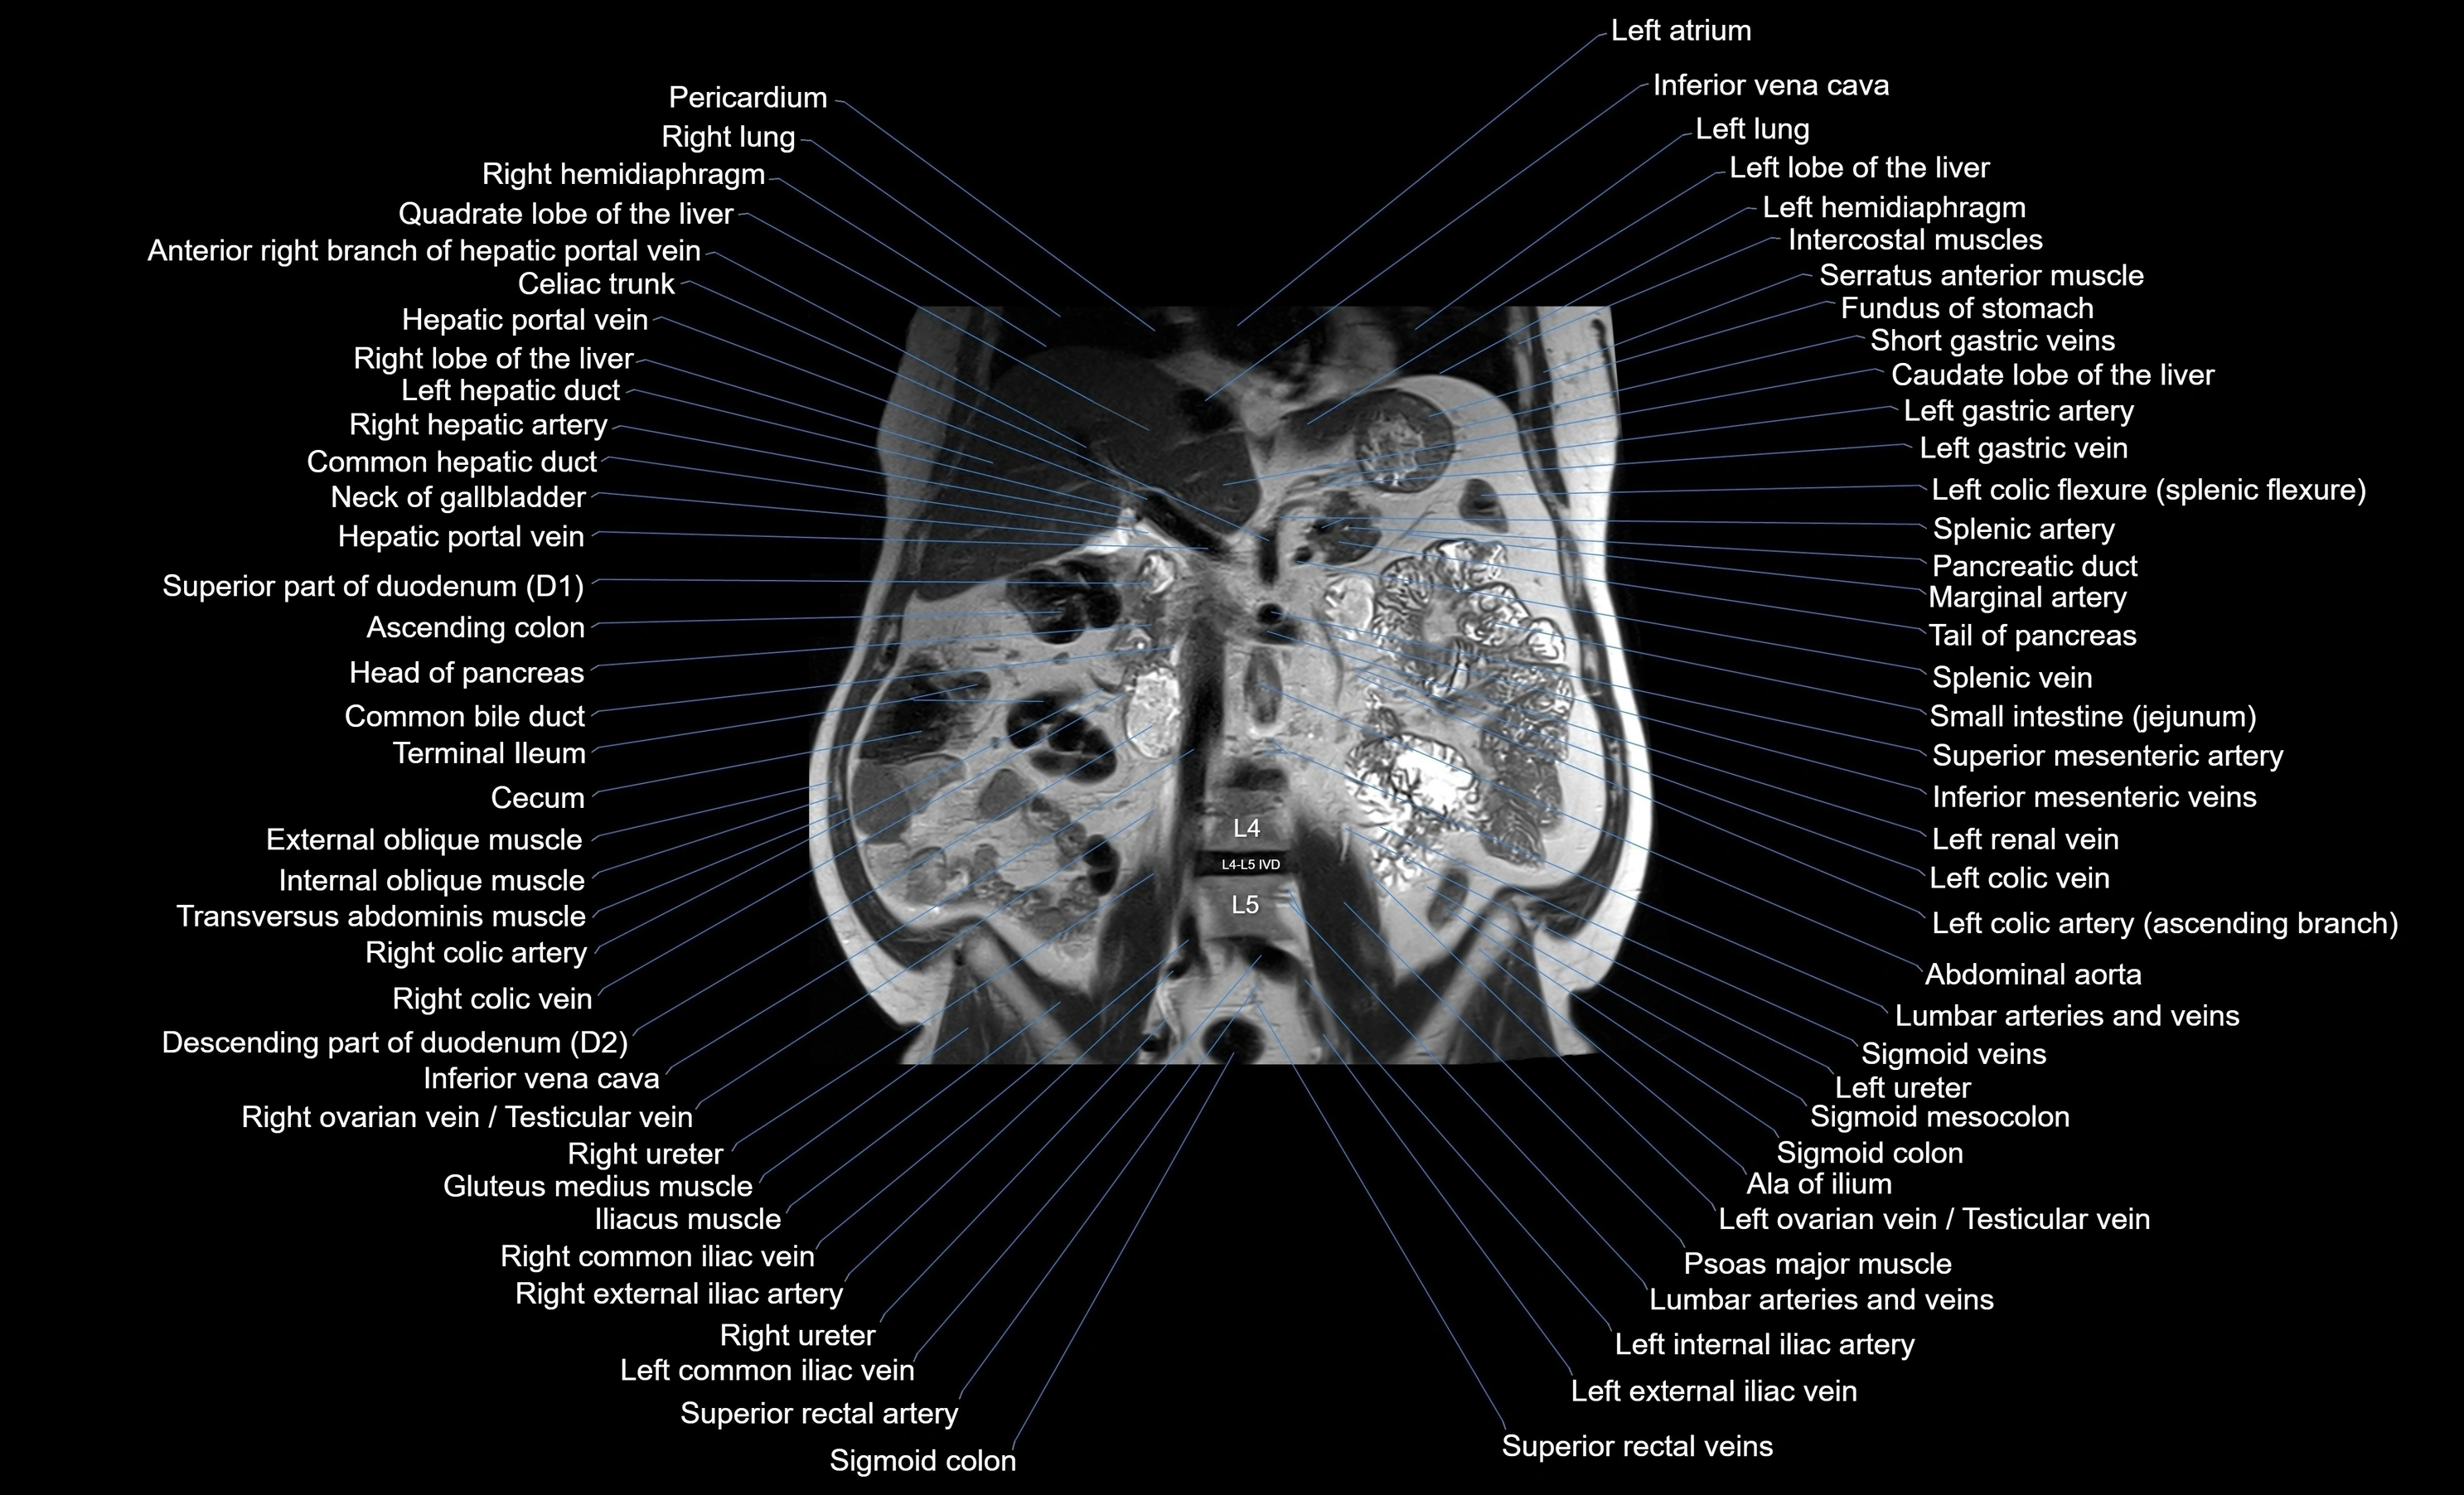

MRI images